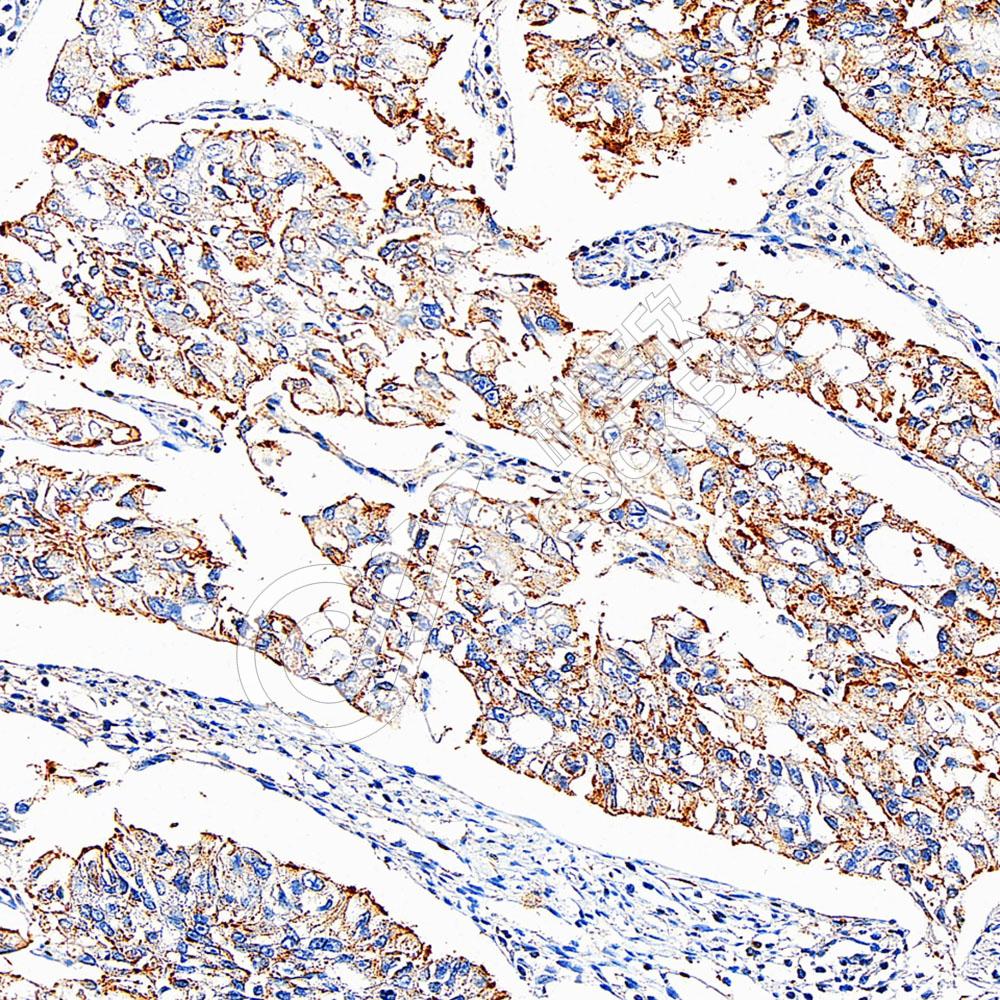

IHC检测Serum Response Factor SRF蛋白(货号 K1333144).

样品: 人胃癌, 4%多聚甲醛 (货号KSG1101) 固定12-24小时.

抗原修复: 柠檬酸抗原修复液(干粉, pH 6.0) (KSG1201), 98℃, 20分钟.

—抗: 1: 1800稀释, 4℃ 孵育过夜.

二抗: S-vision免疫组化多聚二抗(山羊抗兔),即用型 (货号KB3906), 室温孵育20分钟.